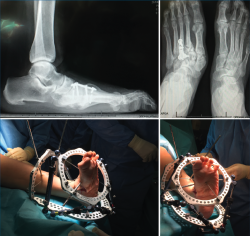

- Cirugía de pie diabético (fijación circular): corrección de deformidades y fijación externa con sistema TSF®(Figura 3).

Figura 3. Corrección de deformidades y fijación externa con sistema TSF®.